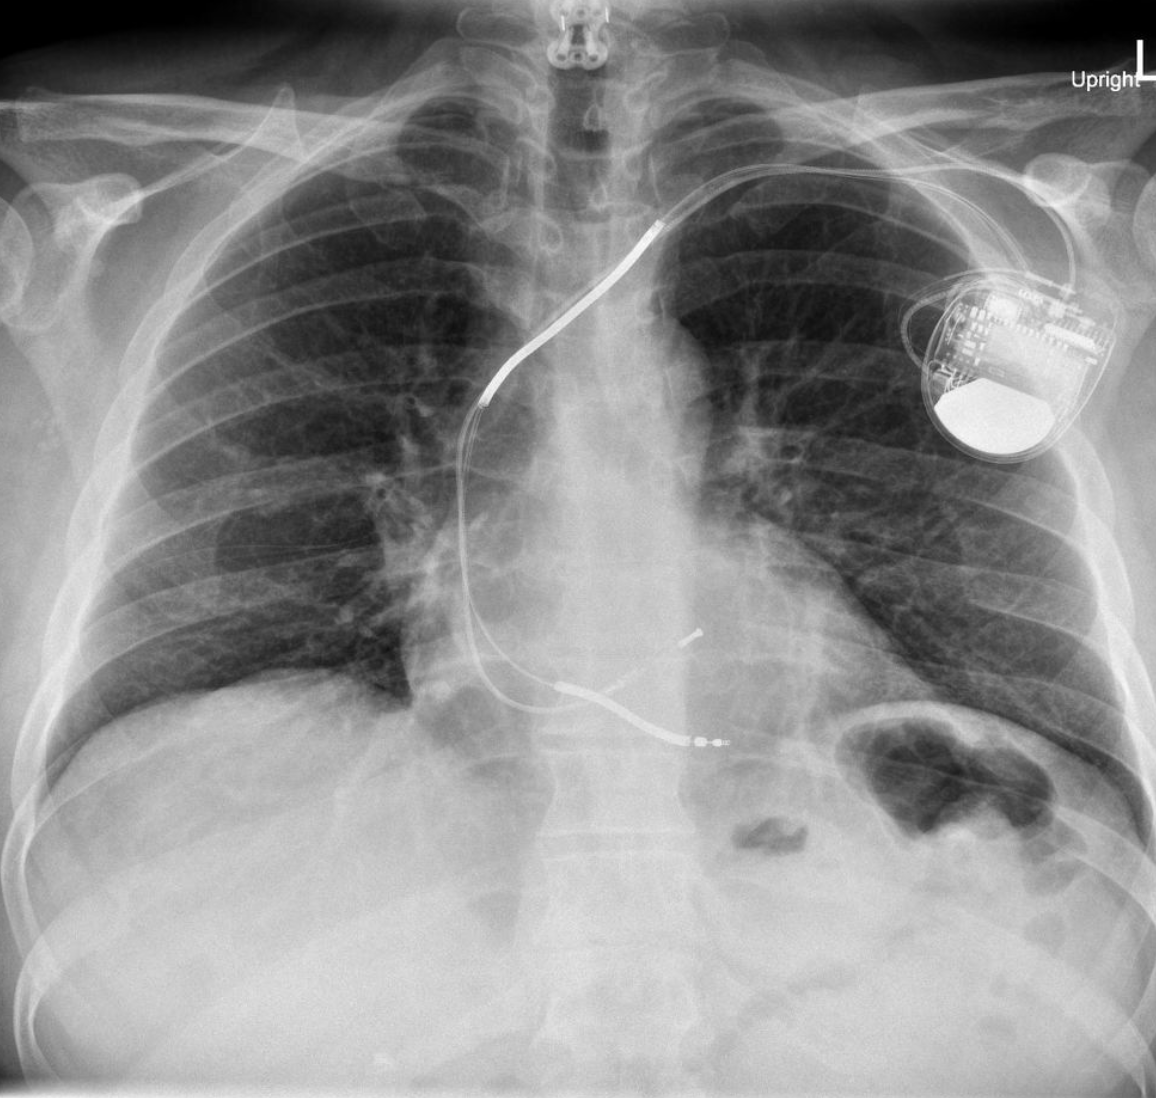

Atrial lead fracture (right by box), right pleural effusion,